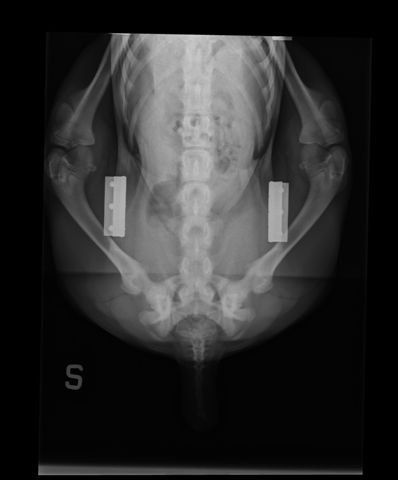

Presso la nostra clinica, la prevenzione della displasia delle anche inizia con uno studio radiografico approfondito, effettuato in anestesia o sedazione controllata. L’esame è sicuro e permette di valutare l’articolazione anche nei cuccioli, già a partire dai 3 mesi e mezzo di età.

- radiografie in più proiezioni (standard, distratta, a rana e DAR);

- valutazione della colonna e, se necessario, anche dei gomiti.